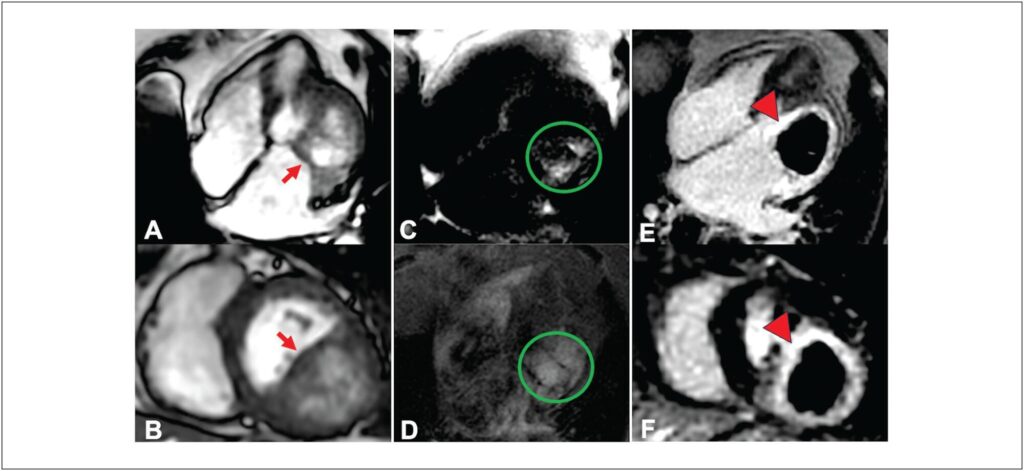

Cardiac masses, though rare, can lead to significant hemodynamic and arrhythmic issues, even if benign. Improved multimodal imaging has refined the diagnosis and understanding of these masses. We present an 85-year-old woman with New York Heart Association class II-III dyspnea for six months. Echocardiography showed a mass in the basal inferolateral wall of the left ventricle, along with severe left atrial dilation and moderate mitral regurgitation. Initially thought to be a pericardial cyst, further cardiac magnetic resonance (CMR) imaging identified an intramyocardial mass, and computed tomography (CT) suggested a hydatid cyst. Given the non-limiting symptoms and high surgical risk, the decision was made for expectant management. This case illustrates the rarity of cardiac cysts and the essential role of multimodal imaging in diagnosis and treatment planning.